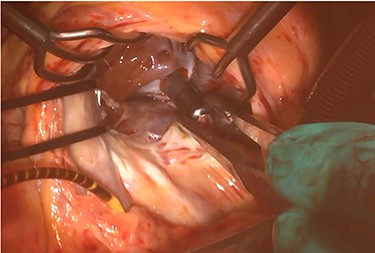

At his 1-year follow-up visit, the patient presented with shortness of breath on exertion and leg edema; thus, we decided to perform surgical correction. After median sternotomy, cardiopulmonary bypass was established with ascending aortic and bicaval venous cannulations. MyoPore (Greatbatch Medical, NY, USA) bipolar sutureless screw-in lead was attached to the left ventricle. A permanent PM was implanted, and left atrial appendage exclusion with AtriClip (AtriCure, OH, USA) was performed afterward. A right atriotomy was performed to facilitate exposure, wherein we found that the septal and posterior leaflets of the tricuspid valve were severely damaged (Fig. 3). Micra was placed over the right ventricular septum and was easily freed under direct vision (Fig. 4). After the leaflets were excised, an Epic (St Jude Medical, MN, USA) 33-mm bioprosthesis was implanted.

Intraoperative photograph; septal and posterior leaflet of tricuspid valve are severely damaged.